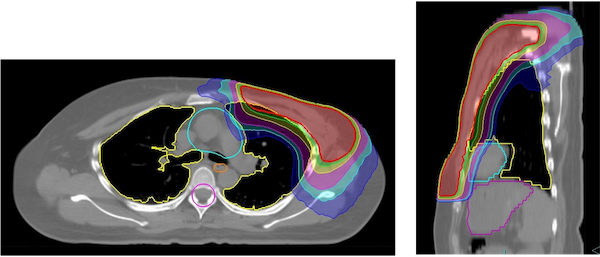

従来、左鎖骨窩のリンパ節と左胸壁に分けて行っていた治療を、つなぎ目なく一度に治療することができるようになりました。